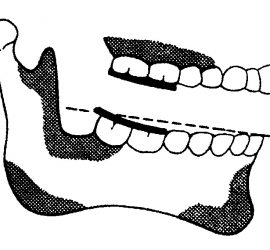

Аппарат представляет собой проволочный нёбный бюгель, который используется для стабилизации положения моляров, после лечения дистализирующими аппаратами, а так же для предотвращения потери места при лечении с удалением зубов. Жёсткая фиксация кнопки Нансе с кольцами создает прочную конструкцию для удержания достигнутого результата лечения.